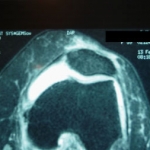

Imagen de RMN de condropatia rotuliana en atleta de 32as. que mejoro con terapia regenerativa.